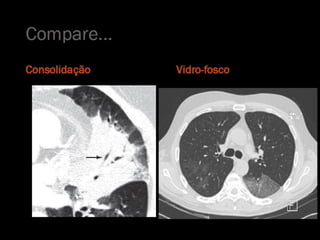

Tomografia computadorizada

   Padrão de vidro fosco;

   Consolidação;

Tomografia computadorizada  Padrão de vidro fosco;  Consolidação;  Padrão Intersticial;  Atelectasia;  Pneumotórax;  Derrame pleural...